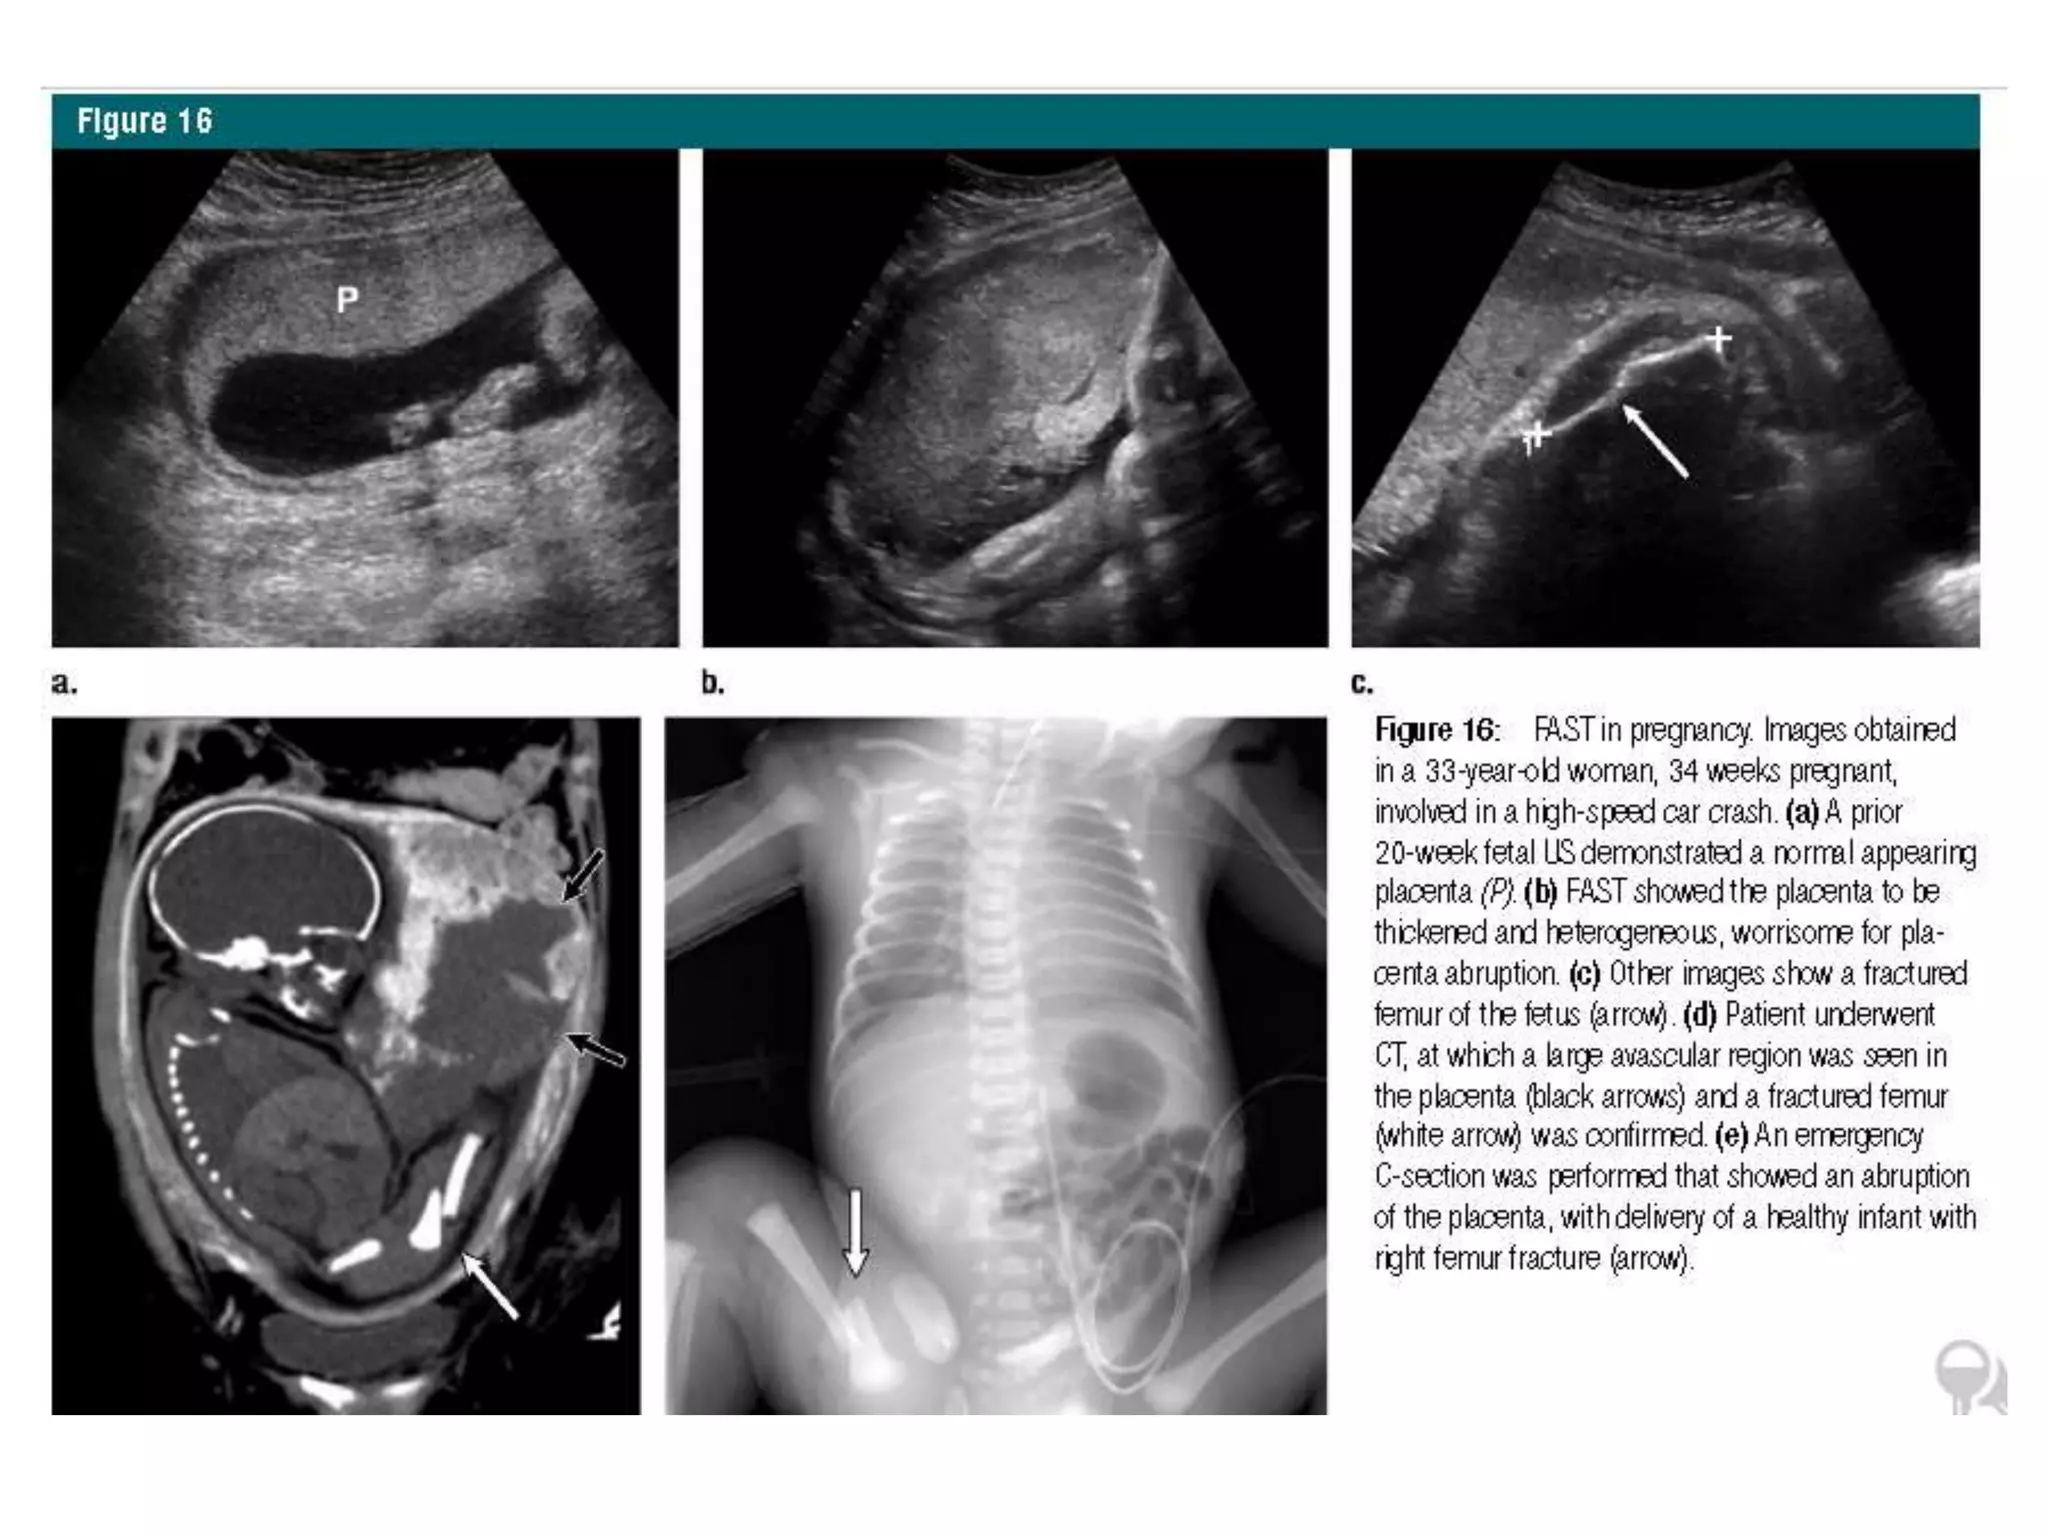

Pregnant Patients

• no contrast material or radiation exposure to

the mother or fetus.

• rapid assessment for free fluid

• assess for fetal heart motion, fetal activity,

amniotic fluid volume, approximate

gestational age, and placenta.

• Similar sensitivity and specificity as non

pregnant

• Placenta examination is very important, as

abruption may have a variety of appearances,

such as thickened or avascular regions in the

placenta without accompanying free fluid in

the pelvis

• Fetal organs and cardiac activity

• Free intraperitoneal fluid may result from

hemorrhage due to solid organ IAI, amniotic

fluid from uterine rupture, or both.

Pregnant Patients • nocontrast material or radiation exposure to the mother or fetus. • rapid assessment for free fluid • assess for fetal heart motion, fetal activity, amniotic fluid volume, approximate gestational age, and placenta. • Similar sensitivity and specificity as non pregnant

• 39.

• Placenta examinationis very important, as abruption may have a variety of appearances, such as thickened or avascular regions in the placenta without accompanying free fluid in the pelvis • Fetal organs and cardiac activity • Free intraperitoneal fluid may result from hemorrhage due to solid organ IAI, amniotic fluid from uterine rupture, or both.